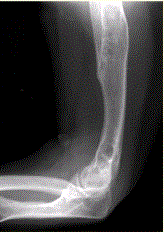

问题 患者男,22岁,长期存在骨和关节变形,近期出现右肘关节疼痛,进行性加重。行右肘关节X线正侧位片检查,见下图。 有关内生软骨瘤(Ollier病),描述正确的是

选项 A.不属于遗传性病变 B.不伴发其他病变 C.常见于女性青少年 D.出现关节疼痛进行性加重对诊断无重要意义 E.伴发软骨发育障碍 F.具有单侧发病倾向

答案 AEF